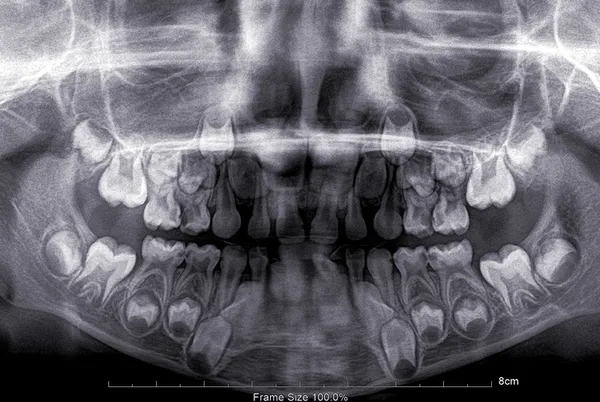

"Çürüğü tamamen önleyebilecek bir uygulama olmasa da koruyup güçlendirmeye yönelik bazı uygulamalar mevcuttur. Bunlardan en yaygın olanı fissür örtücü denilen malzemedir. Fissür örtücüler, fissür adı verilen olukların üzerini kapatarak, o bölgeye yemek artığı ve mikropların sızmasını engeller. Böylelikle çürüğe karşı önlem alınmış olur. Fissür örtücüler, aynı zamanda içerdiği fluorid ile diş yapısını güçlendirmeye destek olur. Bu işlem tüm süt azı dişlerine ve 6 yaşından sonra çıkan kalıcı ve küçük azı dişlerine uygulanabilir.

Çürükle mücadelede bir diğer yol ise fluorid uygulamalarıdır. Fluorid diş macunlarında ve bazı besin maddelerinde bulunur fakat çocuklar çoğunlukla diş fırçalamayı ihmal ettiklerinden yeterli fluorid alamazlar. Bu gibi durumlarda profesyonel yüzeysel fluorid uygulamaları yapılmaktadır. Bu uygulama sadece diş hekimleri tarafından kullanılır ve sadece dişleri çürümeye meyilli çocuklara değil tüm çocuklara yapılabilir."